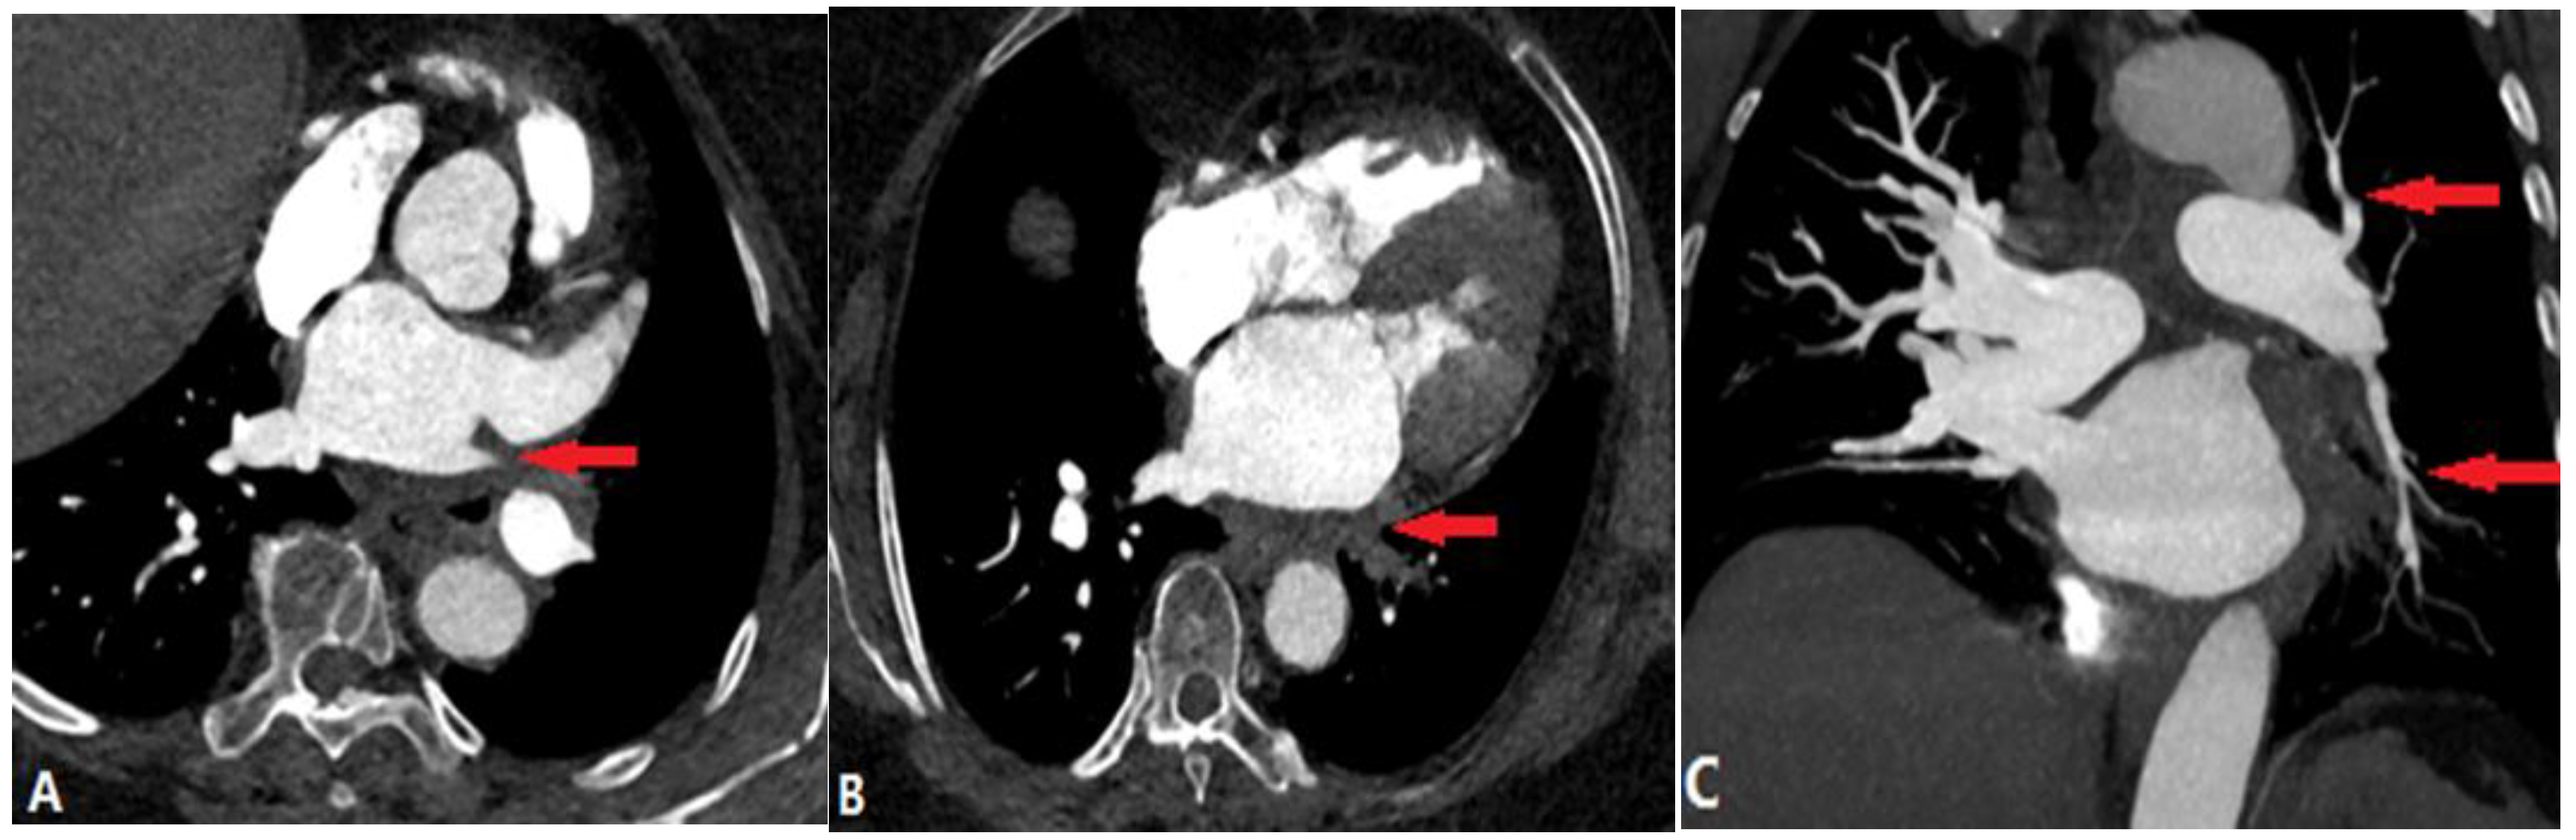

4.3.3. Aortic Aneurysm